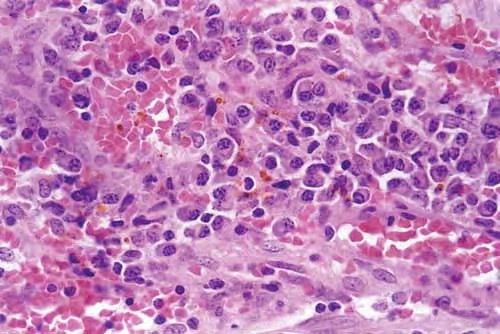

HISTOPATHOLOGY

The histopathology of KS is dependent on the stage of KS development. Early patch-like lesions exhibit rather discrete histopathologic changes, consisting mainly of an increase in the number of dermal vessels, outlined by slightly irregular endothelial cells (Fig. 128-5). These vessels, located mainly in the superficial dermis are parallel to the skin surface, are frequently slightly irregular, and may form bizarre slits and clefts. In the surrounding skin focal hemosiderin, deposits and extravasated erythrocytes can be found as well as a moderate inflammatory infiltrate. Important differential diagnoses of this stage include lymphangioma and granulation tissue.

The pathology of KS plaques is more characteristic and reveals extensive vascular proliferation at all levels of the dermis with multiple dilated and angulated vascular spaces dissecting the collagen leaving a spongy network of collagen tissue. A characteristic sign of KS papules is the presence of solid cords and fascicles of spindle cells arranged between the jagged vascular channels. This biphasic angiomatous and solid tumor morphology changes to a clear-cut sarcomatous morphology with progression of the disease.

Nodular lesions consist predominantly of spindle cells arranged in bundles and interlacing fascicles and interspersed, irregular, slit-like vascular spaces without endothelial linings. Advanced lesions may display pronounced pleomorphism, nuclear atypia, and mitotic figures. At the periphery of solid tumors, (lymph) angiomatous-like portions of KS with bizarre vascular lumina and intravascular and extravasated erythrocytes, as well as siderophages, may be preserved. Erythrocytes, which appear as eosinophilic globules, are trapped within the slits and clefts formed by the spindle cells and erythrophagocytosis are occasionally observed. As in all other stages of KS, a moderate inflammatory infiltrate consisting of lymphocytes, histiocytes, plasma cells, and, sporadically, neutrophils is regularly present.